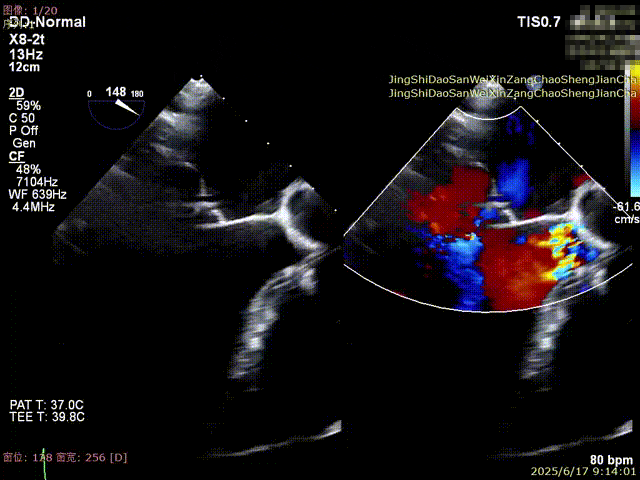

全麻后,首先在心前区的肋间切开3-4CM小切口,暴露心脏的心尖位置,心尖穿刺后进入导丝,利用导丝交换导管鞘完成通路建立。将系统送入左心房,顺利到达二尖瓣病变区域。在经食道超声引导下,术者通过反复评估二尖瓣反流位置、抓捕位置、反流程度,在2区主动脉瓣与二尖瓣闭合线垂直进行巧妙夹合,最终植入一枚ValveClamp®MVC-Ⅲf夹。超声评估夹子固定良好,组织桥完整,无葫芦征,位置、轴向均符合预期。患者术后反流程度从大量转至少量,手术取得圆满成功。患者恢复良好,已经顺利出院。

反流得到明显改善 术后3D动图

术后平均跨瓣压差3mmHg